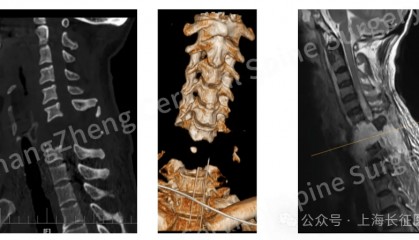

全球罕见!中国医生救回“身首离断”患者 从业近30年,上海长征医院颈椎外科病区主任陈华江教授接诊过无数凶险的颈椎外伤患者,但称得上是“身首离... bitop交易所官网 2025-08-18 23